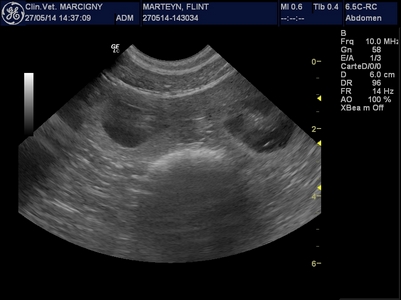

Le mariage de Genkini et Flint'on va porter ses fruits ! De belles petites "bulles de bonheur" nous ont fait coucou lors de l'échographie :-)